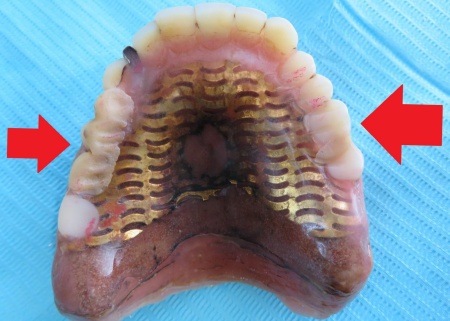

80代男性 経年劣化ですり減った総入れ歯の噛み合わせを調整した症例

- 総入れ歯

- 治療回数の目安 1回

約1,000円

(保険診療1割負担)

・着脱式のため、食後の清掃が必要です ・最初のうちは異物感があり、慣れるまで時間がかかる場合があります ・慣れるまでは、入れ歯の裏側の粘膜に傷ができる場合があります...